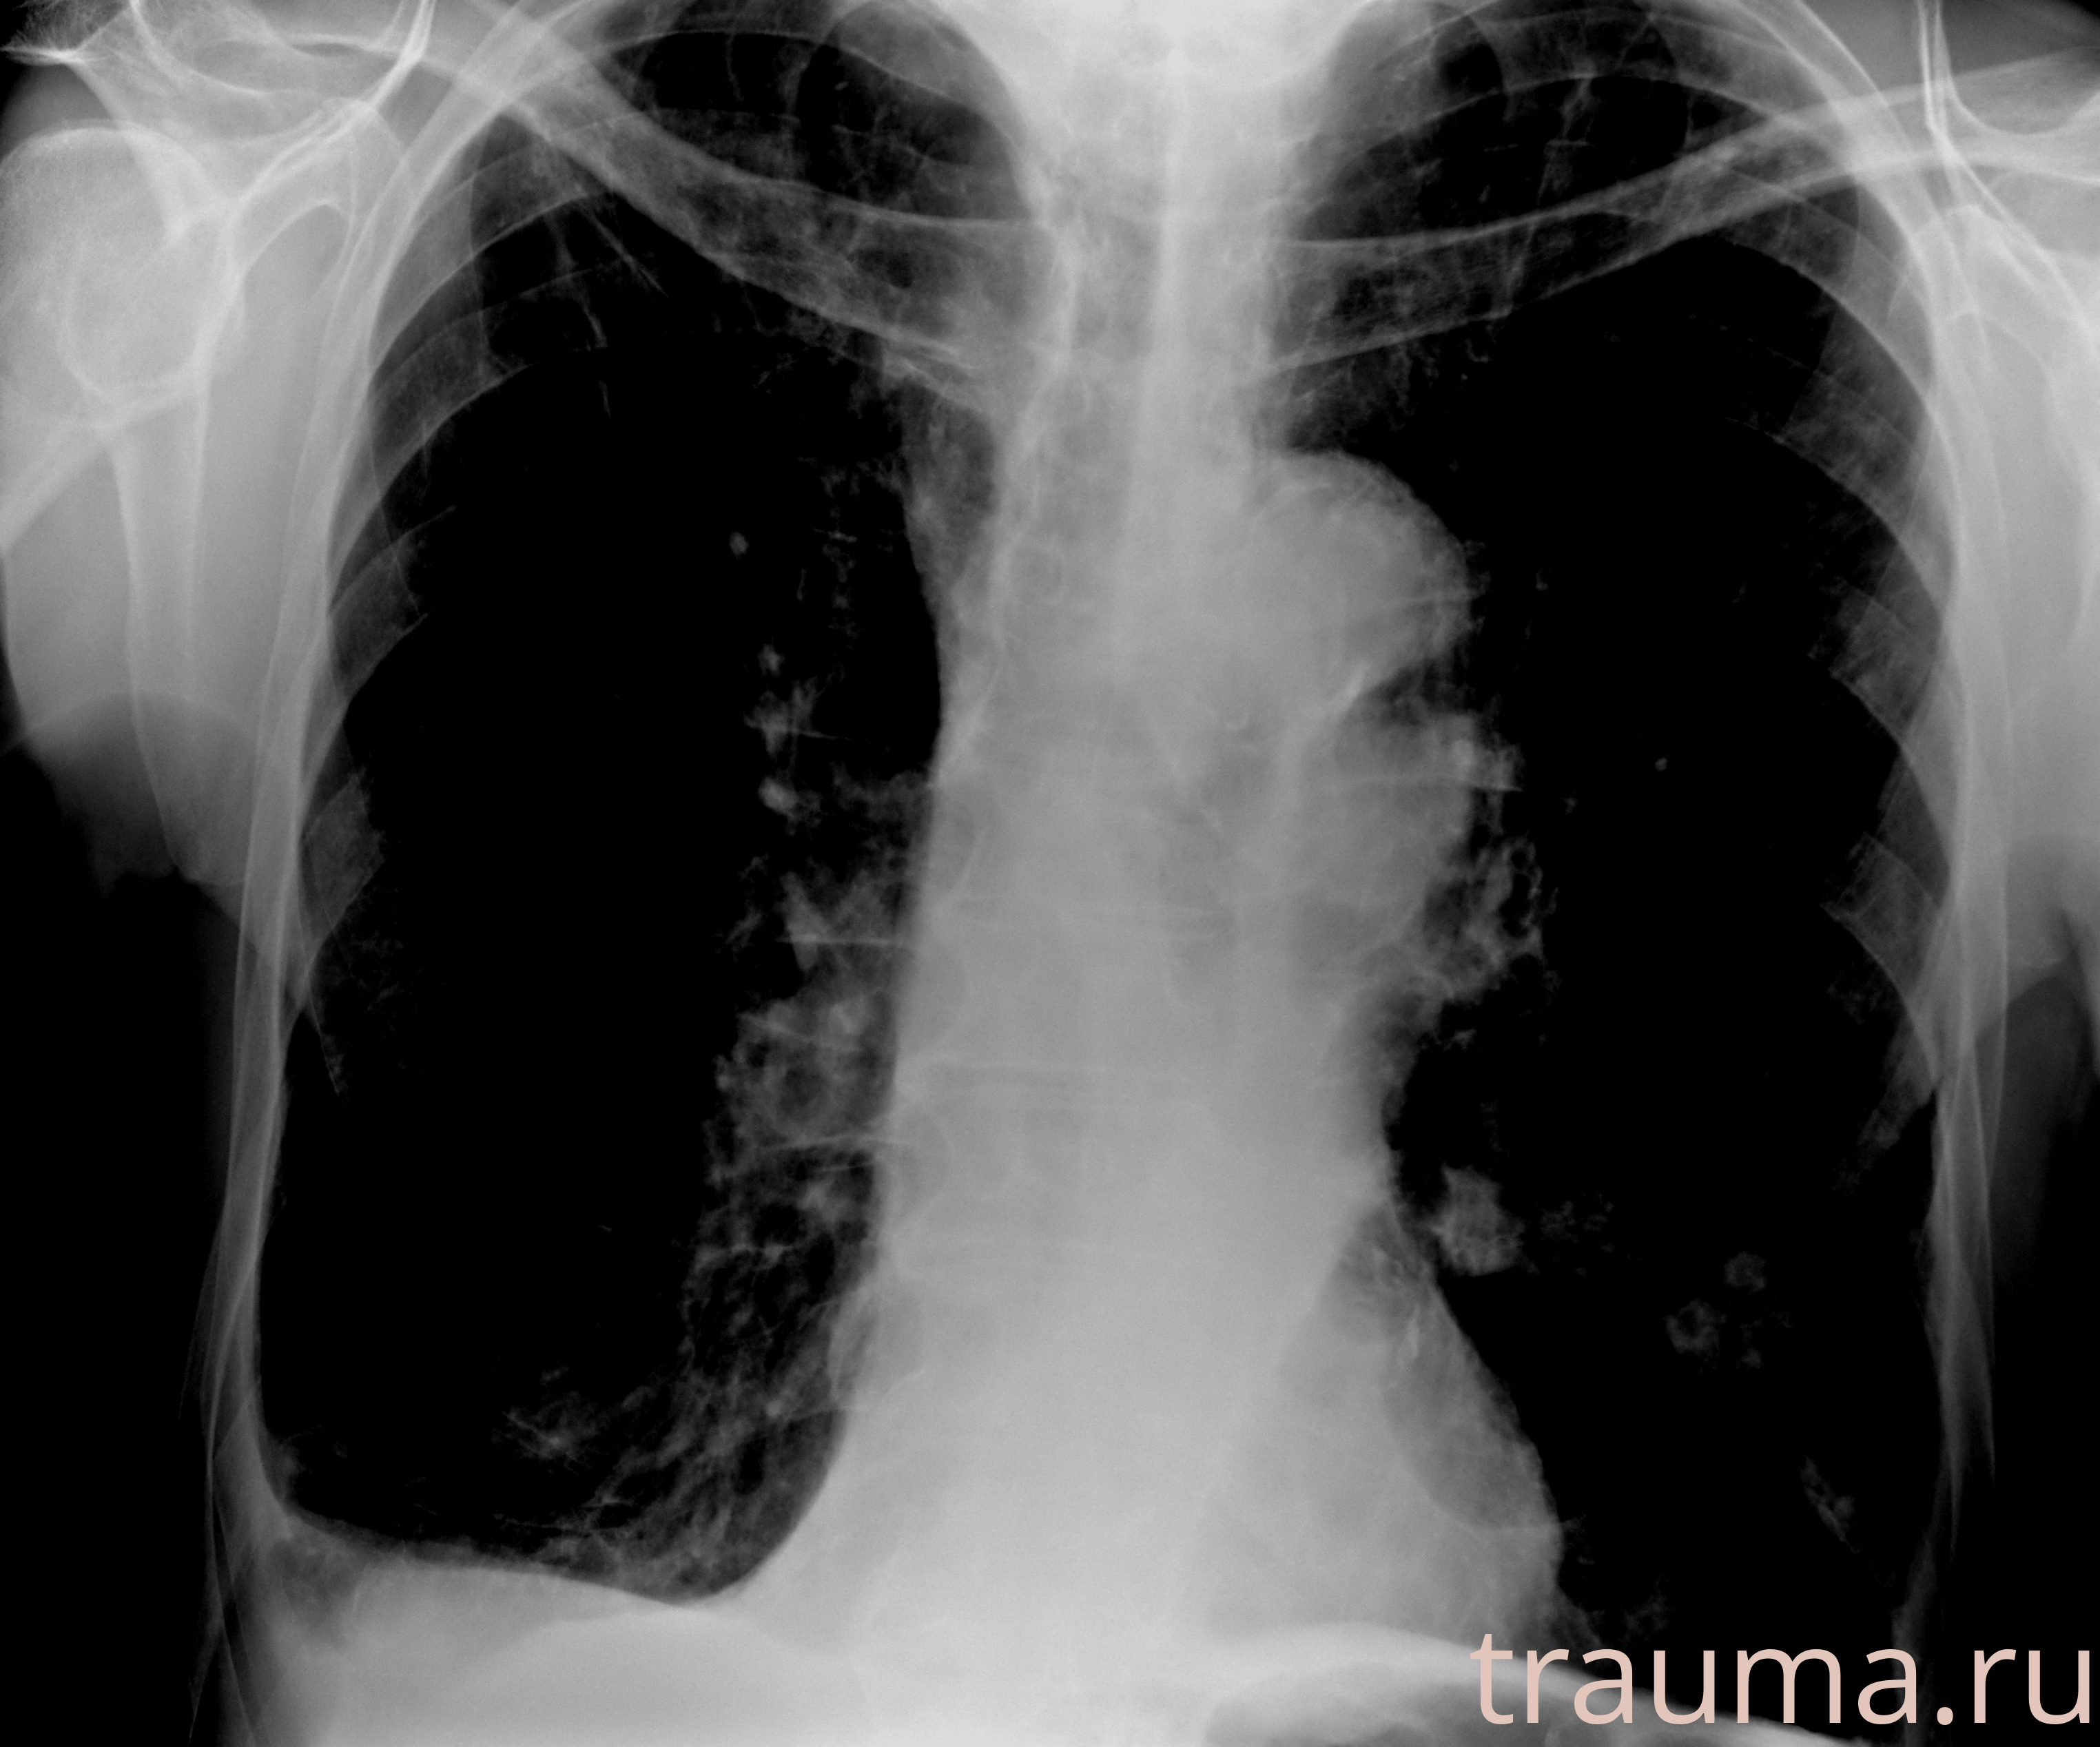

Рентгенограммы

Рентген на дому: по вашему адресу приезжает врач-рентгенолог, травматолог-ортопед с мобильным рентгеновским аппаратом, проводит диагностику травмы или заболевания, делает необходимые рентгенограммы, дает рекомендации по дальнейшему лечению. Получить качественные снимки в домашних условиях возможно благодаря уникальной методике, разработанной МосРентген Центром для института  Склифосовского